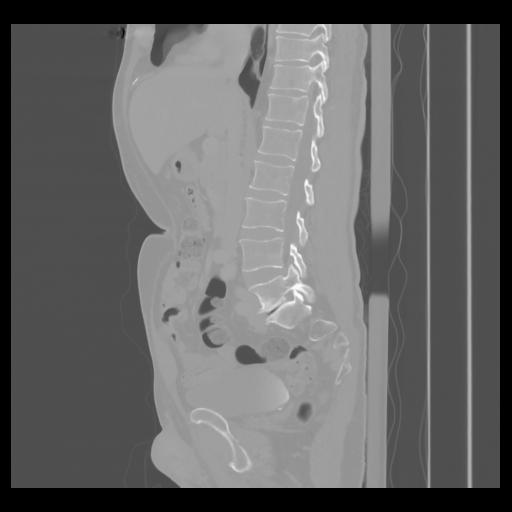

36 CUERPO,CE,Sagittal,3.000,CUERPO,Sagittal,